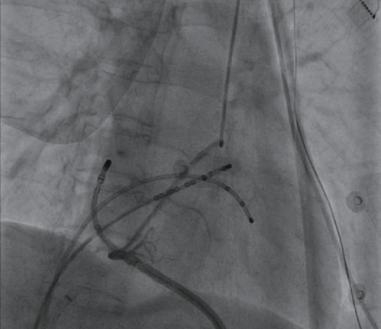

(4)在X线透视下行经皮剑突下心包穿刺术(图2-4-1)。当针头接近心脏轮廓时,推注少许造影剂以判断针尖是否已进入心包腔,证实穿刺心包腔成功后,经穿刺针插入J型长钢丝,置入8F血管鞘至心包腔内。

图2-4-1 置入心室电极后行心包穿刺